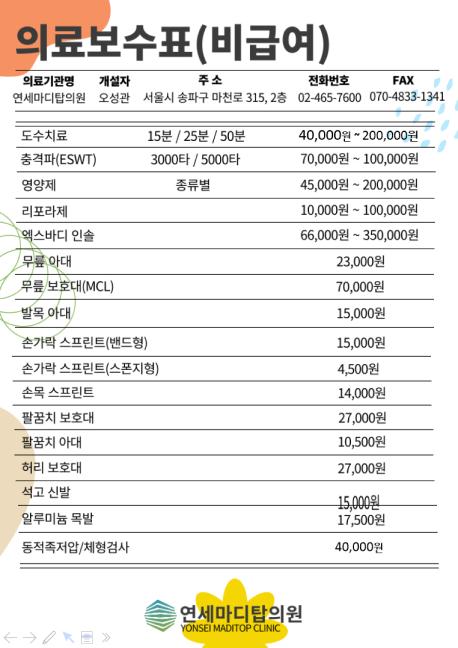

관절클리닉

관절클리닉

어깨통증, 무릎통증, 팔꿈치통증, 수부질환, 족부질환

비수술치료 클리닉

비수술치료 클리닉

도수/물리치료, 운동치료, 수액클리닉

척추클리닉

척추클리닉

목통증, 허리통증

비만통증클리닉

비만통증클리닉

체형 진단 및 운동치료

족부클리닉

족부클리닉

맞춤형 발진단 및 깔창제작